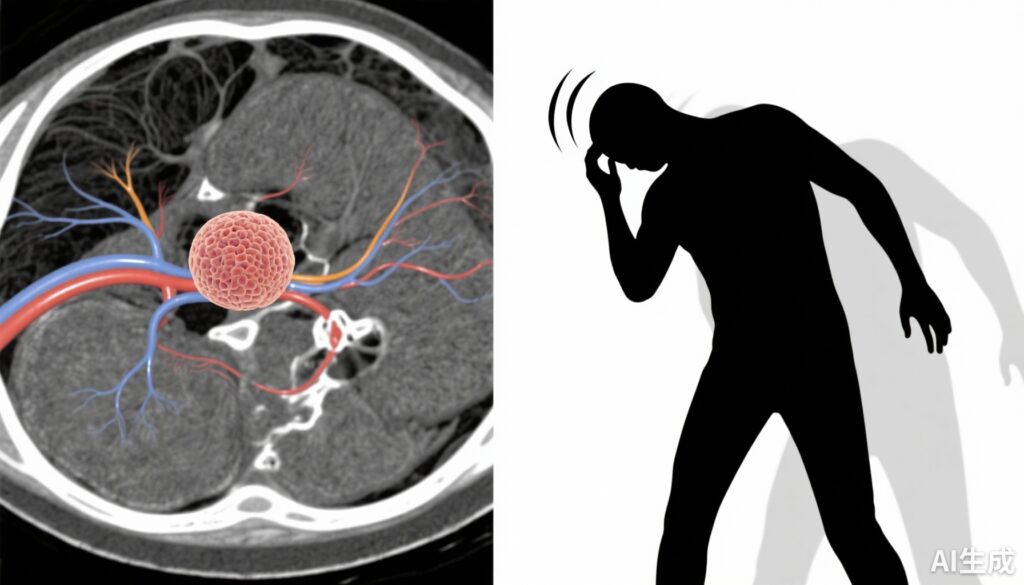

U sợi thần kinh tiền đình (VS), còn được gọi là u thính giác, là một khối u lành tính, thường phát triển chậm, xuất phát từ tế bào Schwann của dây thần kinh tiền đình-thính giác. Bệnh nhân thường gặp phải mất thính lực, ù tai và hoa mắt—những khiếu nại này gây ảnh hưởng đáng kể đến chất lượng cuộc sống. Mặc dù mất thính lực và ù tai đã được nghiên cứu rộng rãi, các yếu tố và đặc điểm của hoa mắt trong VS vẫn chưa được hiểu rõ. Hoa mắt có thể bao gồm chóng mặt, mất thăng bằng hoặc cảm giác không ổn định chủ quan, tất cả đều góp phần vào tình trạng khuyết tật và nguy cơ té ngã. Các yếu tố tâm lý như lo âu phổ biến trong các bệnh lý thần kinh mạn tính và có thể điều chỉnh nhận thức và mức độ nghiêm trọng của triệu chứng. Việc xác định các yếu tố liên quan đến hoa mắt có thể cung cấp thông tin cho việc quản lý triệu chứng tốt hơn và các chiến lược chăm sóc cá nhân hóa.

Nghiên cứu theo dõi hồi cứu này phân tích dữ liệu từ 109 người lớn có VS được xác nhận bằng hình ảnh tại Đại học Washington (St Louis, Missouri) từ tháng 6 năm 2004 đến tháng 1 năm 2025. Tất cả bệnh nhân được bao gồm đã hoàn thành kiểm tra chức năng tiền đình và đánh giá mức độ khó chịu do hoa mắt sử dụng Khảo sát Khó chịu do Hoa mắt (Dizziness Handicap Inventory, DHI), một bảng câu hỏi tự báo cáo đã được kiểm chứng đánh giá tác động vật lý, tình cảm và chức năng của hoa mắt. Mức độ lo âu được định lượng bằng thang đo Rối loạn Lo âu Tổng quát-7 (GAD-7) và qua lịch sử bệnh án về các rối loạn lo âu. Kết quả chính là mức độ nghiêm trọng của hoa mắt, được định nghĩa là điểm DHI liên tục. Phân tích đa biến đã điều chỉnh các yếu tố nhiễu tiềm ẩn để xác định các mối liên quan độc lập giữa các biện pháp lo âu và mức độ nghiêm trọng của hoa mắt.

Tuổi trung bình của nhóm nghiên cứu là 61 tuổi (ĐK 14), với 52% là nữ. Điểm DHI trung bình là 27 (ĐK 24), chỉ ra mức độ khó chịu do hoa mắt nhẹ đến trung bình nhưng có sự biến đổi rộng. Bệnh nhân có tiền sử lo âu có điểm DHI trung bình cao hơn đáng kể 13,7 điểm (95% KTC, 4,2 đến 23,2), phản ánh mức độ nghiêm trọng của hoa mắt cao hơn. Đặc biệt, mỗi điểm tăng trong mức độ lo âu được đo bằng GAD-7, điểm DHI tăng 2,6 điểm (95% KTC, 2,0 đến 3,3), cho thấy mối liên hệ phụ thuộc liều. Sau khi điều chỉnh các biến số như tuổi, giới, kích thước khối u và mất thính lực, mối liên quan vẫn tồn tại với sự tăng 1,9 điểm DHI cho mỗi điểm GAD-7 (95% KTC, 1,3 đến 2,6). Trung bình, tiền sử lo âu có liên quan độc lập với mức độ khó chịu do hoa mắt cao hơn 10,6 điểm (95% KTC, 2,4 đến 18,7). Những kết quả này nhấn mạnh mối liên hệ vững chắc giữa lo âu và gánh nặng hoa mắt chủ quan ở bệnh nhân VS.